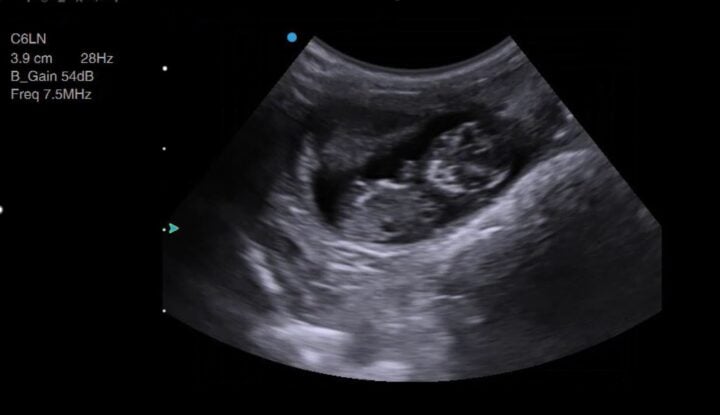

Intestines or gestation sacs? Manipulating the imaging plane

Once you have identified and looked around the bladder and as you begin to move your transducer cranially, you will encounter either more gestation sacs or the intestines (Figure 2) in the “normal” bitch or queen. Intestines are one of the great pitfalls of pregnancy scanning and are mistaken for gestation sacs more often than you might care to believe. The key is to rotate your transducer 90 degrees to confirm whether the circular structure you are seeing is indeed spherical (ie an early gestation sac).

If you are an experienced user of ultrasound, this will be easy and intuitive. But if you are new to ultrasound, this is a skill that is worth practising at every opportunity, as you will use this same movement to image the long and short axis of the foetus and almost every structure and organ you examine using ultrasound.

Manipulating your imaging plane is essential for certain measurements, such as crown–rump length and biparietal diameter. Still images can be ambiguous – Figure 3, for example, is not pregnancy – so watching a video clip (Video 1) instead makes this image more interpretable.